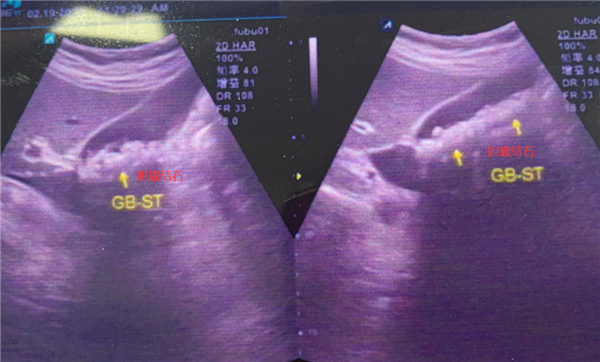

京都醫(yī)院檢查提示,涂婆婆膽囊里有近300顆結(jié)石,最大的有1公分左右。如果繼續(xù)放任不管,結(jié)石將會在涂婆婆膽囊內(nèi)越長越多

經(jīng)過一個多小時的手術(shù),成功經(jīng)患者肚臍眼位置取出297顆金黃色的小結(jié)石,乍眼看去就像一顆顆“玉米粒”似的,最重要的是,膽囊由于功能完好也被順利保住了!